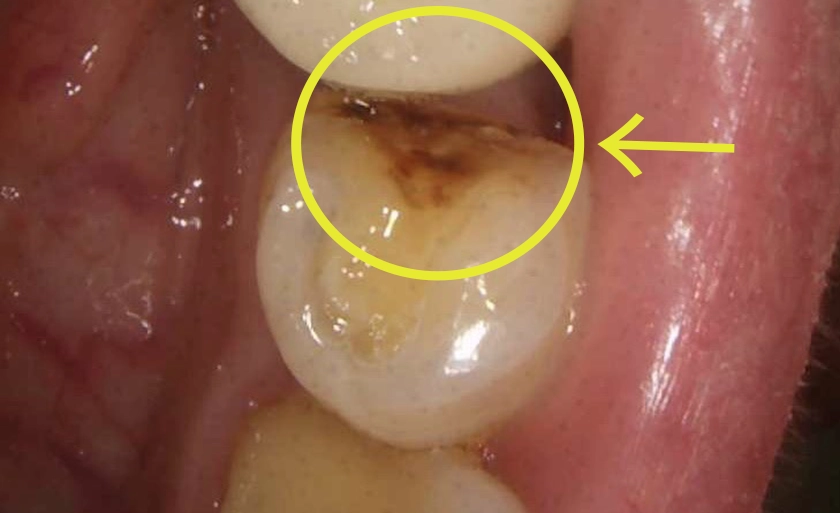

虫歯を削った歯にレジン(複合樹脂)を直接詰める治療法です。保険診療では、15〜30分の限られた時間内で、保険制度で定められた範囲内の基本的な処置のみを行うことになります。

保険診療との具体的な違い

保険診療は接着剤1滴のみ。ダイレクトボンディングは前処理を行い密着力を大幅に向上。